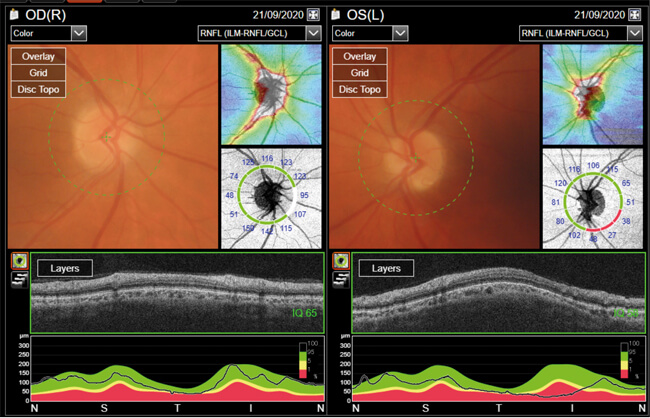

Figure 2: The patient showed no obvious optic nerve swelling.

This is a complex situation, however, there is no obvious optic nerve swelling (Figure 2) and no transient visual obscurations. The reduced vision in the left eye could be explained by the previous NAION. There are no signs of GCA at the moment and the raised inflammatory markers are likely to be malignancy related with possible underlying infection process as they responded well to Tazocin.